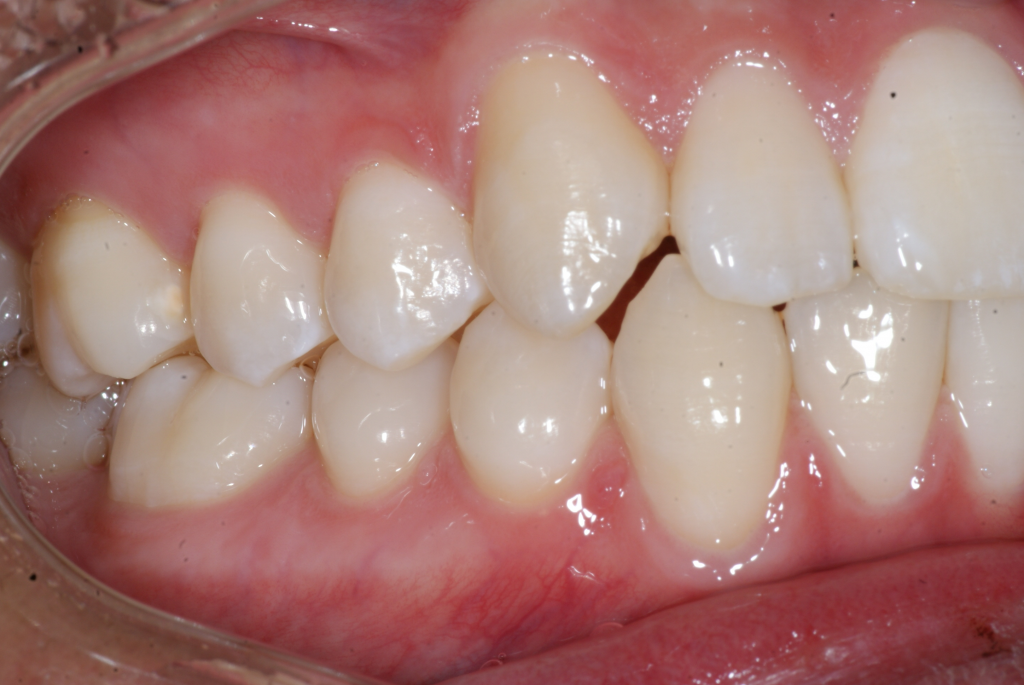

Correction d’une malocclusion de type bimax, canine #33 ectopique et chevauchement léger aux 2 arcades.  Des appareils fixes (broches) et extraction de 4 prémolaires furent nécessaires pour améliorer ce sourire.  Traitement chez un jeune adulte, réalisé en 28 mois.